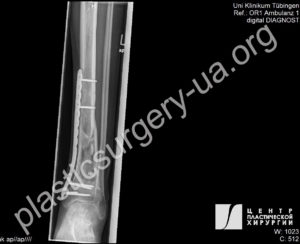

Рис. 37. Фото комбинированного повреждения левой нижней конечности в результате ДТП.

При поступлении в клинику определяется обширный раневой дефект и перелом костей голени В3 с дефектом большеберцовой кости до 11 см. Отломки кости стабилизированы в аппарате внеочагового остеосинтеза. Рис. 38. Результат реконструкции через 4 месяца; рана голени закрыта свободным антеролатеральным перфорантным лоскутом (ALT), размерами 21х10 см, гранулирующая рана стопы закрыта пересадкой кожного расщепленного трансплантата.

Рис. 39. Рентгенограмма левой голени после закрытия дефекта лоскутом. На рентгенограмме определяется открытый оскольчатый перелом 3В ст. костей левой голени, тень избыточных мягких тканей лоскута в нижней 13 голени. Рис. 40. Рентгенограмма левой голени через 24 месяца после травмы. После билокального ЧКДО определяется восстановленный методом дистракционного остеогенеза дефект большеберцовой кости; формирующийся костный анкилоз голеностопного сустава; сросшиеся переломы дистальной 1/3 диафизов обеих костей голени; в дистальном отделе синостоз костей голени. Лодыжки отсутствуют и своими дистальными концами образуют ложные суставы с таранной костью; остеопороз. Опорная функция нижней конечности восстановлена, пациент самостоятельно ходит без дополнительной опоры.